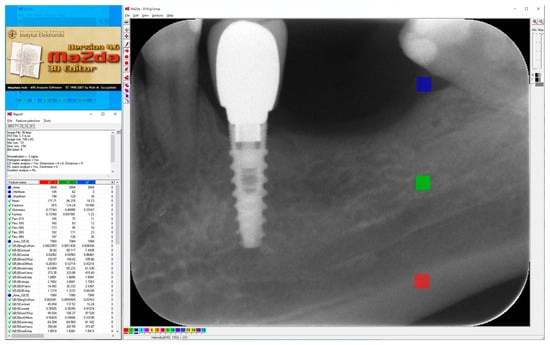

Square areas of 3844 pixels (62 × 62), i.e., regions of interest (ROIs) in 8-bit, greyscale images were included in the study, numbering 40 for the compact (cortical) bone images, 40 for the cancellous (trabecular) bone images and 40 soft tissue images (Figure 1). A total of 120 ROIs were analyzed.

Figure 1.

Regions of interest were located in cortical bone (ROI 1), trabecular bone (ROI 2) and soft tissue (ROI 3) in main window of MaZda. Next, a series of textural features was extracted (MZ Reports—on the left) and exported in comma-separated vector format (CSV).